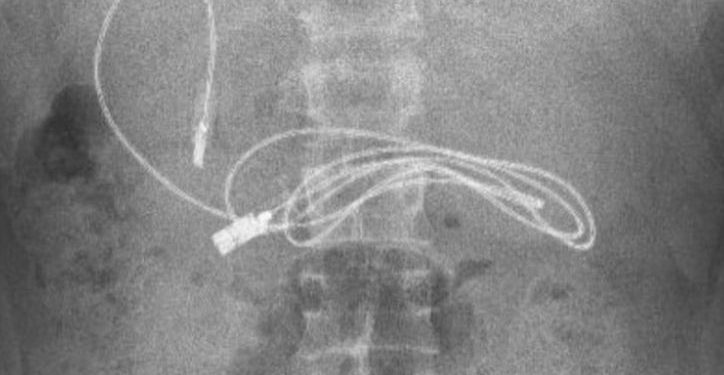

ოპერაციის შემდეგ, ექიმებმა მას მუცლიდან 91.44 სმ სიგრძის USB კაბელი ამოუღეს.